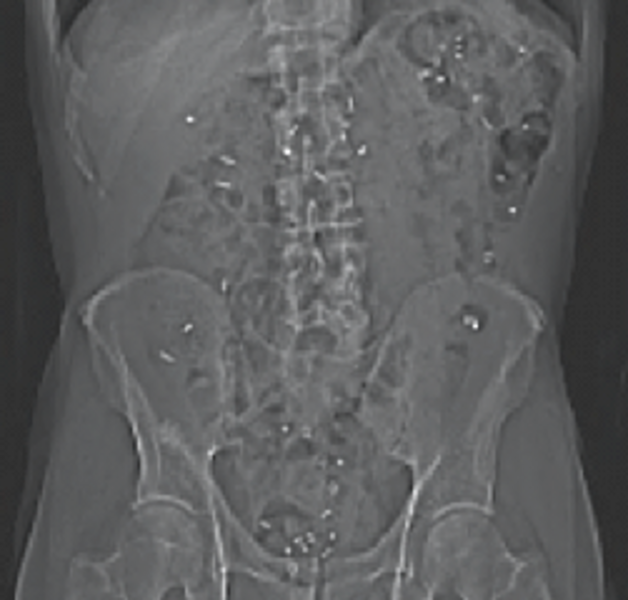

CT scanning of the abdomen

Every morning for 6 days a capsule containing 10 very small plastic markers, which the intestine cannot absorb, is ingested. The number of remaining markers in the intestine on the day of the scan can be converted into transit time through the gastrointestinal tract. This is thus a measure of intestinal function and particularly intestinal peristalsis (intestinal movements). Likewise, on this scan, the volume of the colon can be analysed as another measure of intestinal function and constipation.

Every morning for 6 days, a capsule containing 10 very small plastic markers (radiopaque) is ingested. The plastic markers cannot be absorbed from the intestines. The number of retained markers in the intestines reflects the intestinal transit time. Many patients with PD display increased intestinal transit time, which is an objective marker of constipation.